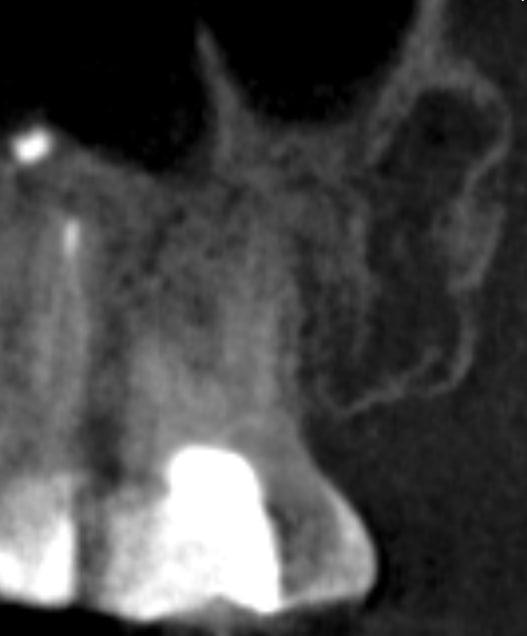

И так зуб ранее уже был леченым, небольшие неприятные ощущения все время были, чуть больше месяца назад вскрыли, последний канал долго не могли пройти, но 2 недели назад распломбировали таки, уже много раз мыли, чистили каждый раз прикрывали временной пломбой, есть кт до вскытия каналов, и есть снимок после открытия всех 3, с гуттаперчей делали снимок.

Помогите пожалуйста понять, в чем дело. из за чего сохраняется боль при накусывании, а так же если шевелить пальцами зуб в стороны (не с не с большой силой конечно же), а так же сохраняется произвольная боль в течении дня, при нагрузке физической и эмоциональной, интенсивность конечно немного меньше чем 2-3 недели назад, но она есть, я бы не сказал что прям легкая. Доктор специализируется в том числе на корневых каналах, я понимаю что боль из-за сохраняющегося воспаления, но каковы причины его, и как быть ?